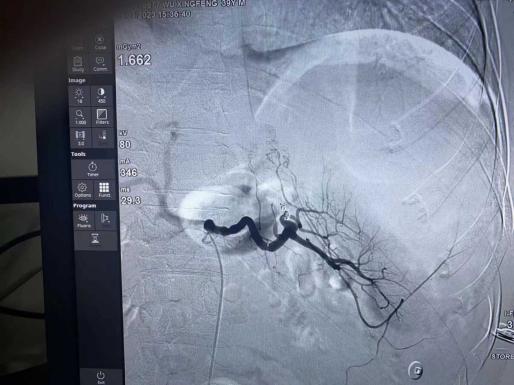

急性白血病属于血液系统恶性疾病,异质性高,进展迅速,早期死亡率高。就在患者家属还在等待正式结果,商议是否治疗的时候,患者因为高肿瘤负荷,脾髓外造血破裂,造成“肿瘤溶解综合征”伴应激后原有的糖尿病血糖异常波动,出现了“糖尿病酮症酸中毒伴昏迷”。性命攸关时刻,高瑛副主任医师迅速指导抢救,内分泌科、超声室、心电图室、输血科、肝胆外科、CT室均开启了急诊患者救治的绿色通道,血液内科同海宁护士长加入抢救,启动科室危重患者紧急救治的绿色通道。经过抢救,患者3个小时后神志恢复,影像检查明确脾脏破裂,因为血小板极低,凝血异常,生命体征不平稳,外科无法开展手术。就在患者出现失血性休克,家属商议准备放弃治疗的时候,高瑛医疗小组与介入科陈思攀主任沟通病情后,陈思攀主任虽患病休息,仍迅速与科室诊疗小组商讨,颜昭勇医师充分评估患者情况,与手术室和麻醉科协调后,在输血科血制品的保驾护航下,再次为这位患者开启了紧急救治绿色通道。经过2个小时的“脾动脉栓塞术”,患者手术成功,安返病房。高瑛医疗小组与护理责任小组细致观察病情,及时根据病情调整治疗方案,同时不忘人文关怀,充分与患者和家属沟通,尽可能减轻患者紧张情绪,消除家属焦虑思想。医护患三方共同配合,生命体征平稳后开启了“减瘤”治疗。目前患者病情平稳,已经进入了常规诱导治疗阶段。